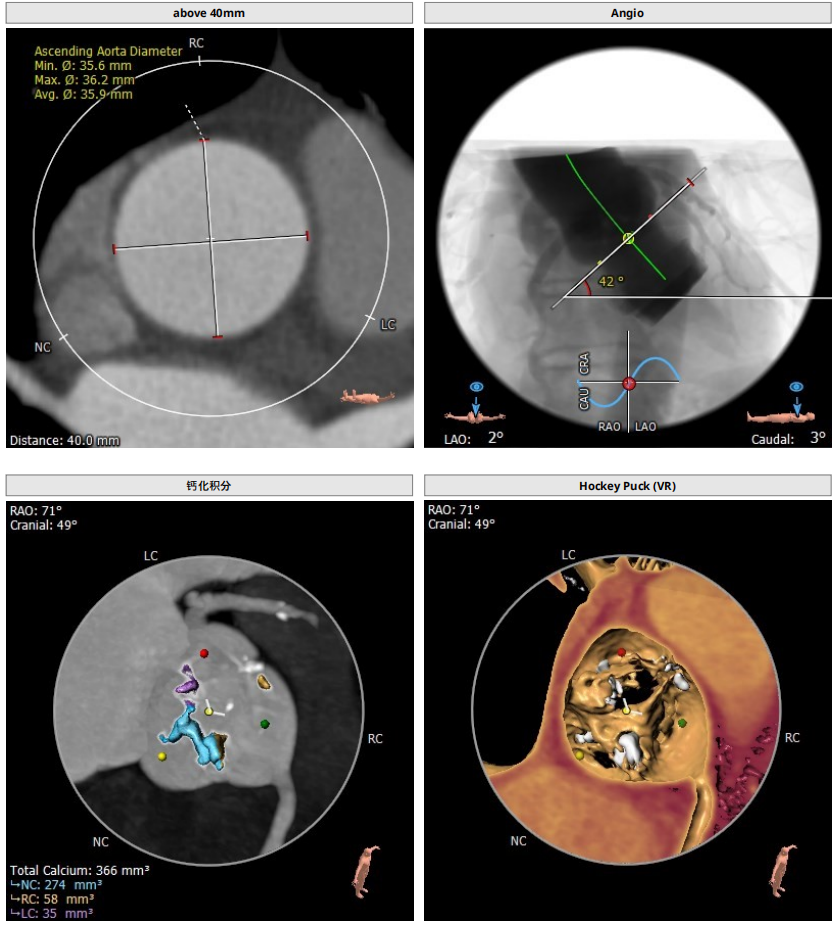

CT分析

以3个窦消失最低点确认的平面作为虚拟瓣环平面初步筛选瓣膜尺寸。自展瓣参考周长得出的Annulus直径,该病人为25.8,根据自膨胀瓣膜特点需要oversize,初步判断为29/32瓣膜。LVOT直径大于Annulus,短径24mm,足够限制瓣膜,提供锚定支撑力。STJ高度足够,可提供足够空间给原有瓣叶,过宽的STJ则无法提供释放中锚定支撑力。

窦部的空间与左右冠脉开口高度结合瓣叶形态,是否增厚可以初步判断瓣叶是否会在瓣膜植入后遮挡冠脉开口造成急性的冠脉堵塞。该病人左冠开口略低,且钙化集中在右冠和无冠窦,判断冠脉风险较高。需术中球扩判断是否进行冠脉保护。

升主动脉未见增宽,心脏角度合适极重度钙化,多集中在基底部位二叶瓣重度钙化THV需要downsize选择26/29瓣膜。

钙化积分:

0-400 轻度

400-600 中度

600-800 重度

800以上 极重度钙化

投照角度:左冠切线位球囊扩张时采用,可以观察左冠是否有冠脉风险,工作体位三窦平均拉开,无冠窦位于最低处方便瓣膜释放和定位心室大。

入路:入路观察是否有溃疡、钙化、迂曲、血管狭窄等情况,以判断夹层风险。该病人入路情况良好,优先选择右股作为输送系统主入路。